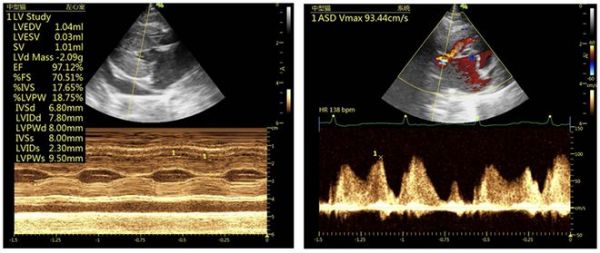

图4:右侧长轴四腔心 图5:右侧长轴四腔心

图6:右侧长轴五腔心

9.1 心脏超声结果分析

心超M-mode可见左心室舒张末期室中隔厚度约6.8mm,左室壁厚度约:7.8mm,均超过6 mm,提示肥厚性心肌病;左心房与主动脉内径比值约1.9(正常<1.5),提示左心房扩张,左心前负荷升高,有比较高的肺水肿风险。另外房间隔处存在左向右分流,存在房间隔缺损的情况,同时在心脏周围可见少量游离液性暗区,提示存在胸腔积液。